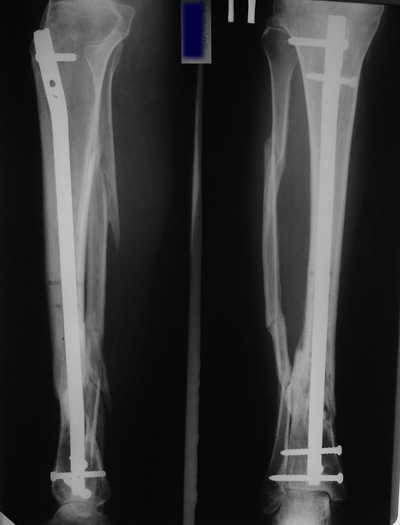

Male 54 years old, diabetic, blind in both eyes, with infected (MRSA) non union distal tibia after fracture 8 month ago. In acute phase treated by ORIF with LCP tibia and fibula. Treatment complicated by infection and after 6 month hardware was removed and treatment continued by cast fixation. You can see malposition of fragments In this stage beginning treated by Ilizarov fixation with use Hexapod system, allows anatomical position of fragments and you see signs of union.

Sorry, I wiil tray now pictures of my case.